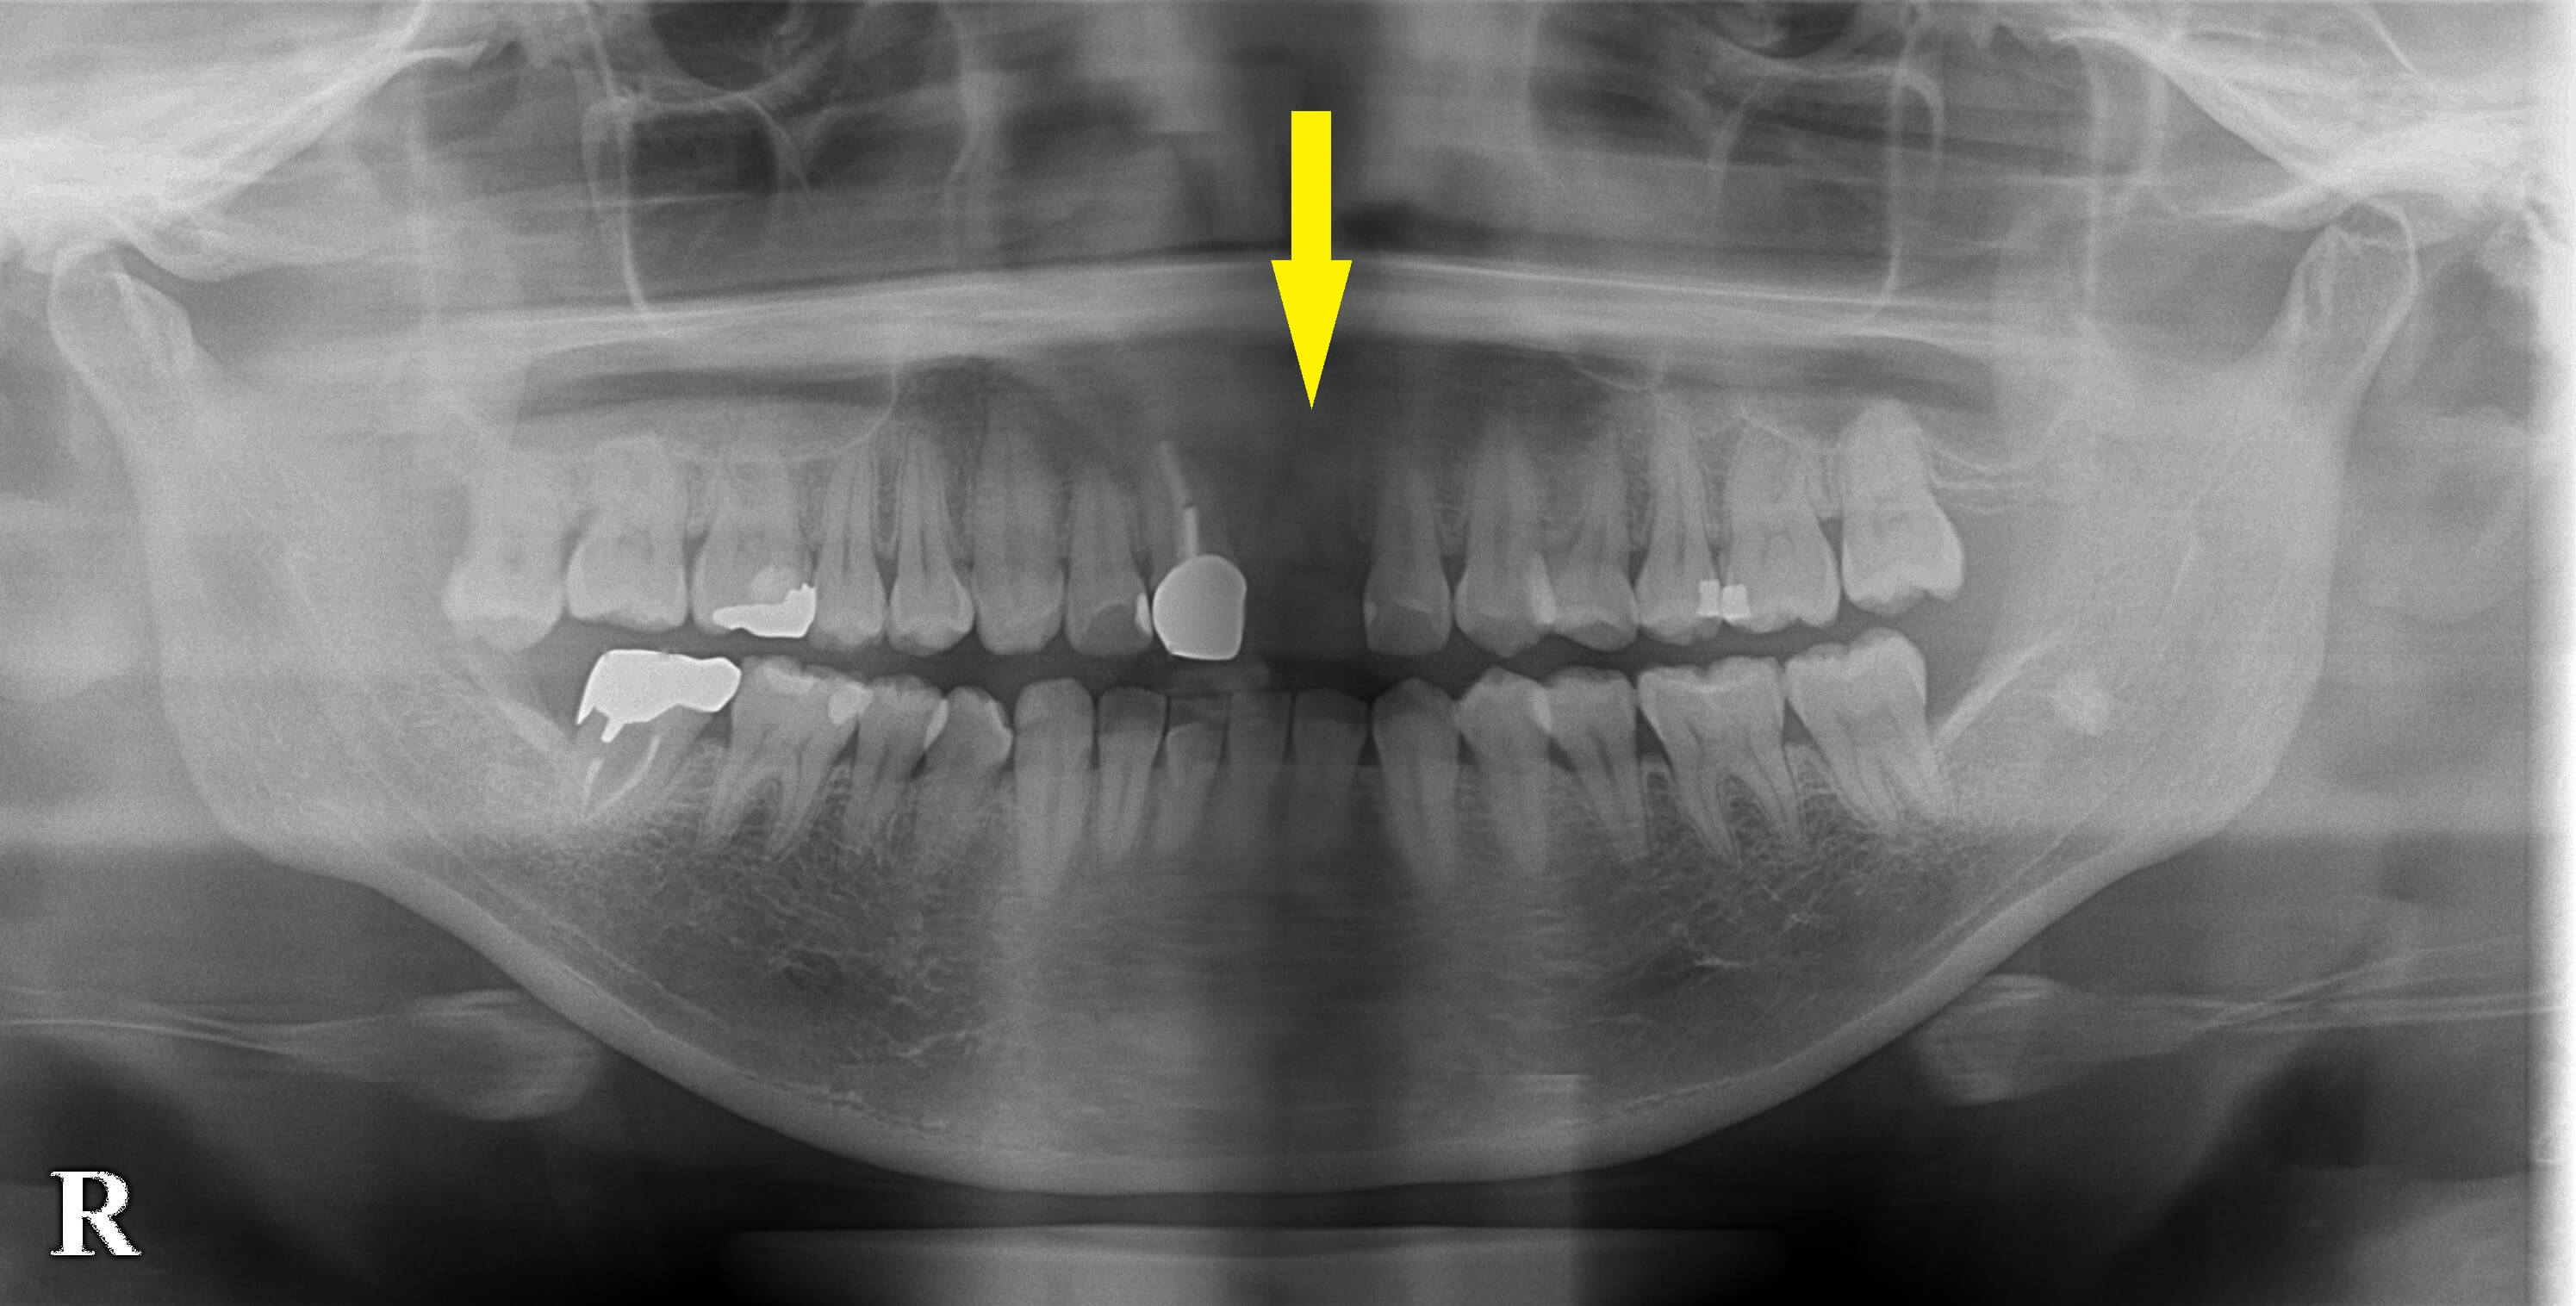

患者様は名古屋在住の30代女性。

上顎前歯の歯根が破折してしまって、抜歯され、インプラント治療を希望して当院に相談においでになりました。

CTで見ると、抜歯されたばかりの歯の跡の外側に、ごく薄い骨が残っているのですが、これは、数か月で吸収してなくなってしまいます。

そこで、この骨がまだ少しでも残っているうちに、インプラントを埋入して、

人工骨を補填しておくと、大きく骨が吸収されてしまうのを防止できますので、早めのインプラント埋入手術をお勧めしました。

同意をいただけましたので、本日、抜歯後、早期インプラント埋入術および、骨造成術を行いました。

下の写真、下段左が手術前のCT、右が手術後のCTです。

埋入したインプラントの外側は人工骨で覆われています。